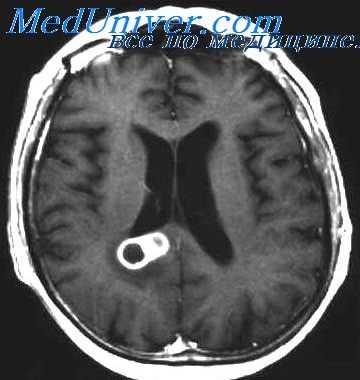

В последние годы для окончательного уточнения диагноза проводится компьютерная томография, хотя она еще далеко не везде доступна. Этот метод позволяет точно определить локализацию абсцесса, его размеры, глубину расположения, перифокальный отек мозговой ткани, перивентрикулярный отек.